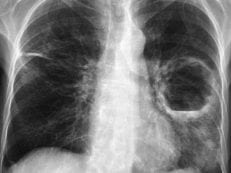

Неспецифический воспалительный процесс ткани легкого, вследствие которого формируется гнойно-некротическая полость, называется абсцессом. Выделяют два типа течения заболевания: острый и хронический. При отсутствии своевременного лечения или под влиянием провоцирующих факторов возможно развитие разного рода осложнений.

Осложнения острого абсцесса легкого

При благоприятном течении, заболевание продолжается не более 6 недель, после дренажа или прорыва полости остается небольшая тонкостенная киста. При наличии сопутствующих патологий или при некачественном лечении развиваются следующие осложнения: